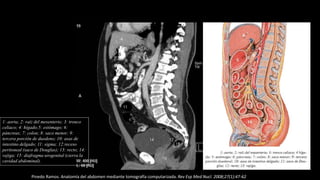

Pinedo Ramos. Anatomía del abdomen mediante tomografía computarizada. Rev Esp Med Nucl. 2008;27(1):47-62

1: aorta; 2: raíz del mesenterio; 3: tronco

celiaco; 4: hígado;5: estómago; 6:

páncreas; 7: colon; 8: saco menor; 9:

tercera porción de duodeno; 10: asas de

intestino delgado; 11: sigma; 12:receso

peritoneal (saco de Douglas); 13: recto; 14:

vejiga; 15: diafragma urogenital (cierra la

cavidad abdominal).